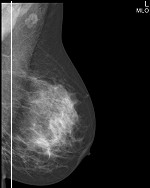

30多年前,吉特模拟乳腺摄影系统就为乳腺病人提供服务。世界范围内不计其数的装机量见证了吉特的图像质量和操纵性能。基于最新的模拟数字化技术和圆形臂机架杰出的操纵性能,吉特模拟乳腺摄影系统是一套基于屏片应用的模拟数字化乳腺检查尖端设备。

艾蒙斯研发的圆形臂独特外形和人体工程学的控制按钮面板,使得操作更为人性化。

优势:三维摆位,让受检者自然放松前倾斜靠于机架,自然舒适地暴露更多乳腺组织进入投照视野。

灵活的选择:站位、坐位(轮椅)、仰卧;超出2 cm乳后组织显像!